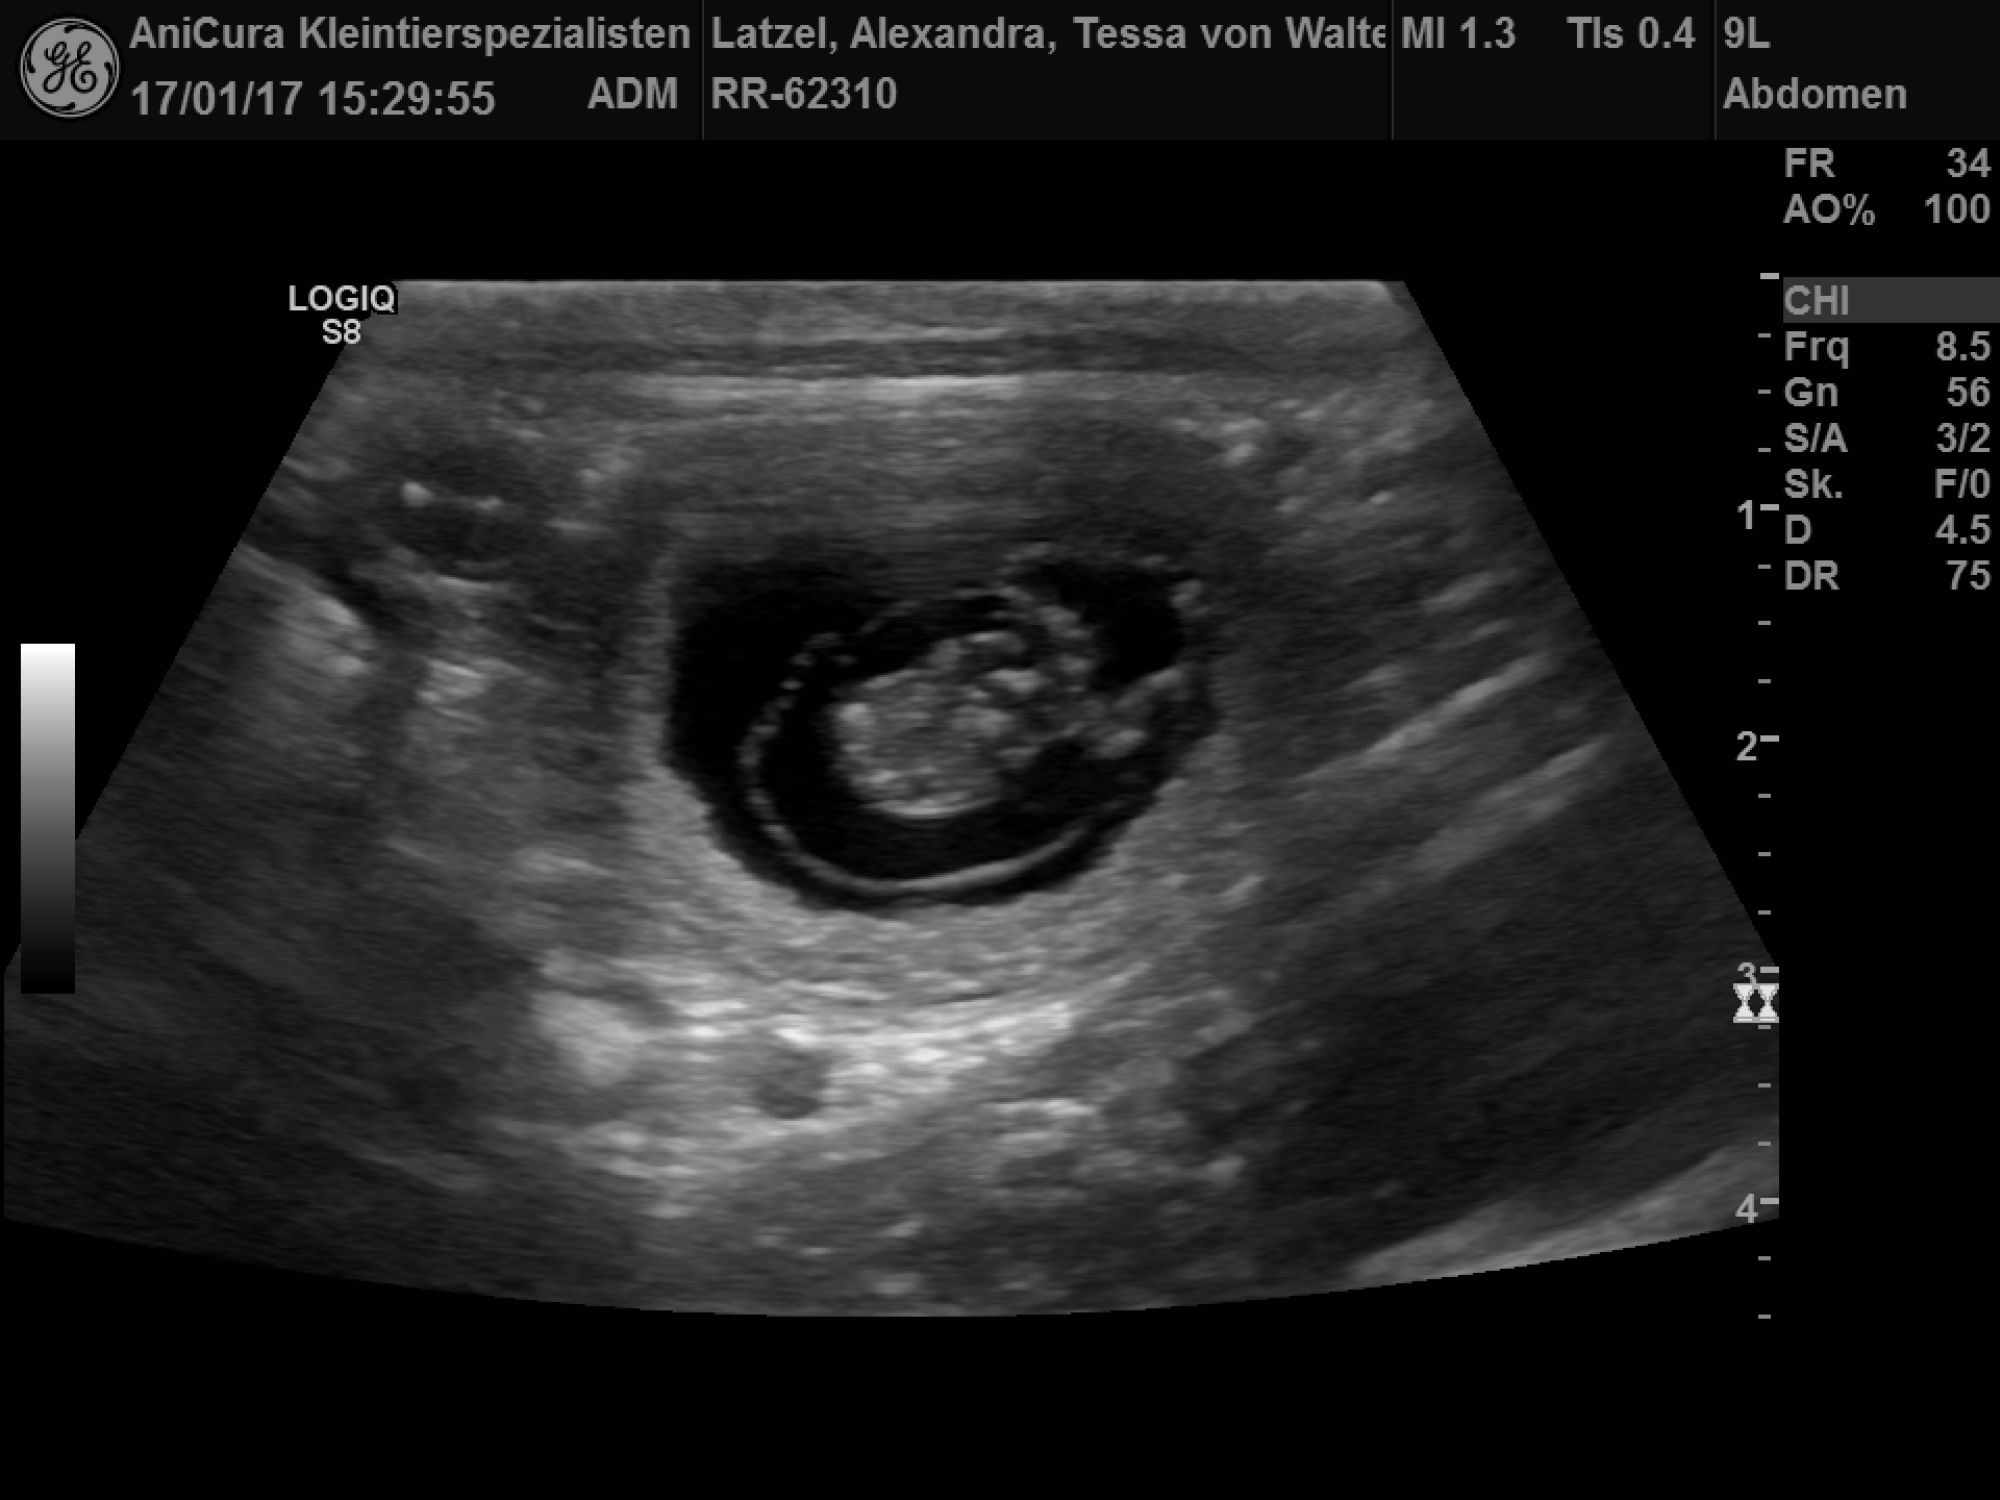

| 17.01.2017 |

| Tessa ist Schwanger! Die Ultraschallbilder beweisen es! |